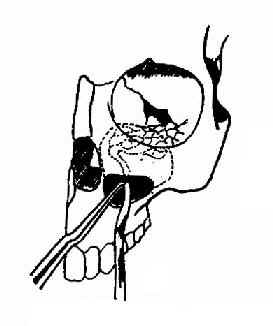

开放性骨折可自创口伸入钝钩或剥离器将骨片复位,彻底清创,去除异物及碎屑,并于下鼻道前下凿一对孔通入上颌窦,填入碘仿纱条,自对孔引出,缝合伤口。3~5d后自鼻腔抽出纱条。闭合性前壁塌陷骨折,颧弓或眶底骨折者,可自颧弓上或眶下作切口,进行骨折复位。也可按照上颌窦根治手术作切口进入窦内,用钝性器械将骨折复位,清理窦内异物及碎骨片,自下鼻道行对孔引流,窦内填入碘仿纱条固定下陷的骨折。3~5d后,自前鼻孔内抽出纱条(图13-7,13-8)。

图13-8 上颌窦上壁骨折的复位法